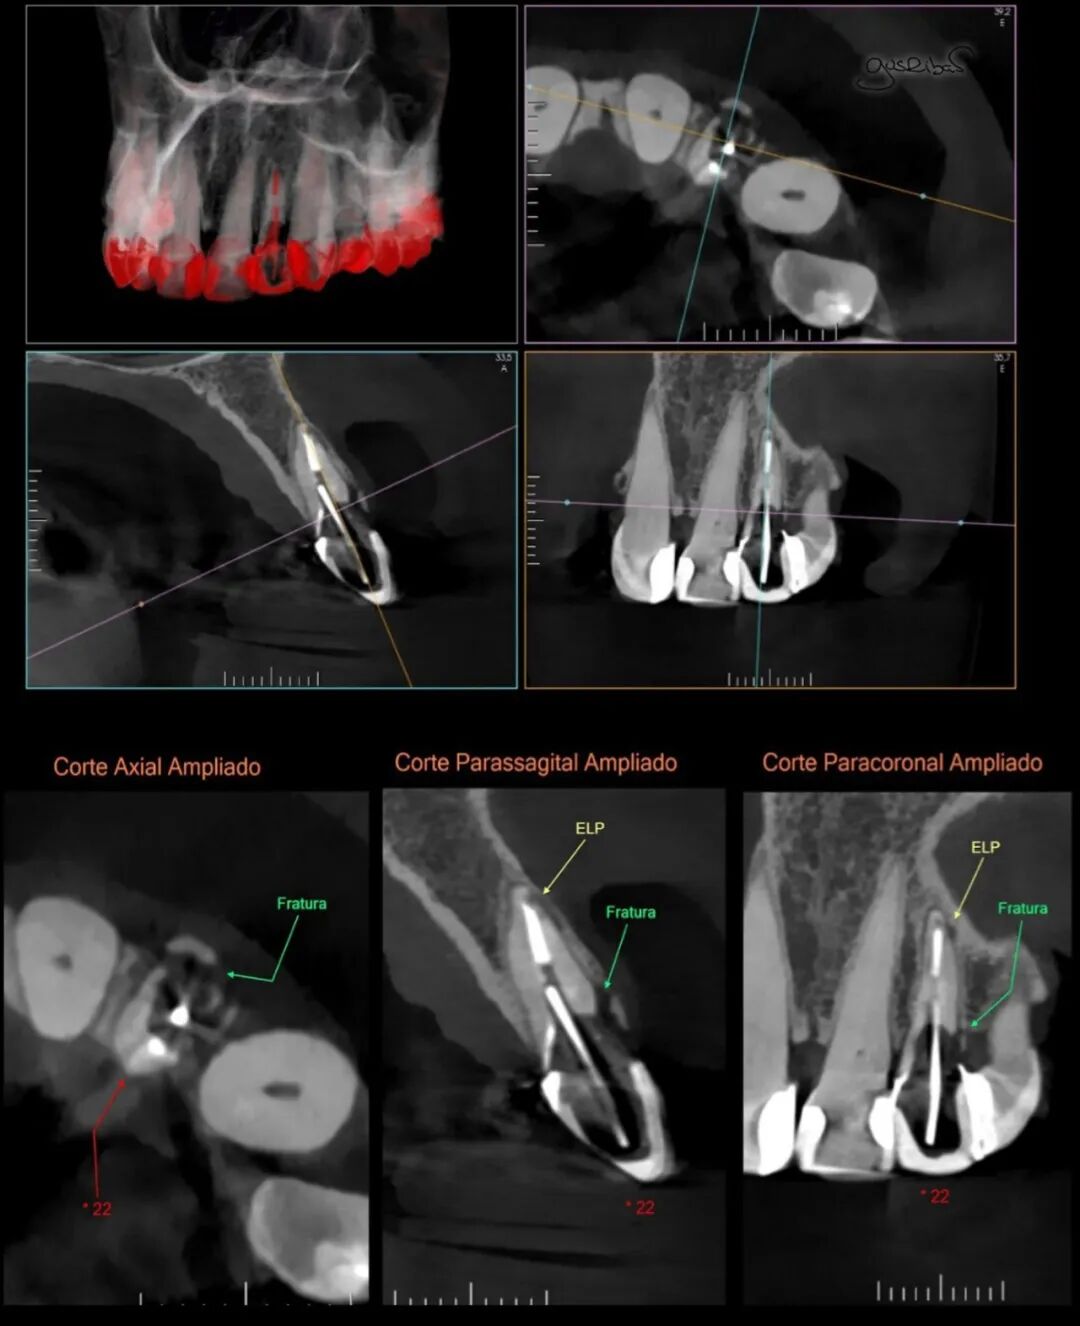

考虑到患者颌骨骨坏死的风险很高,没有进行任何侵入性手术,